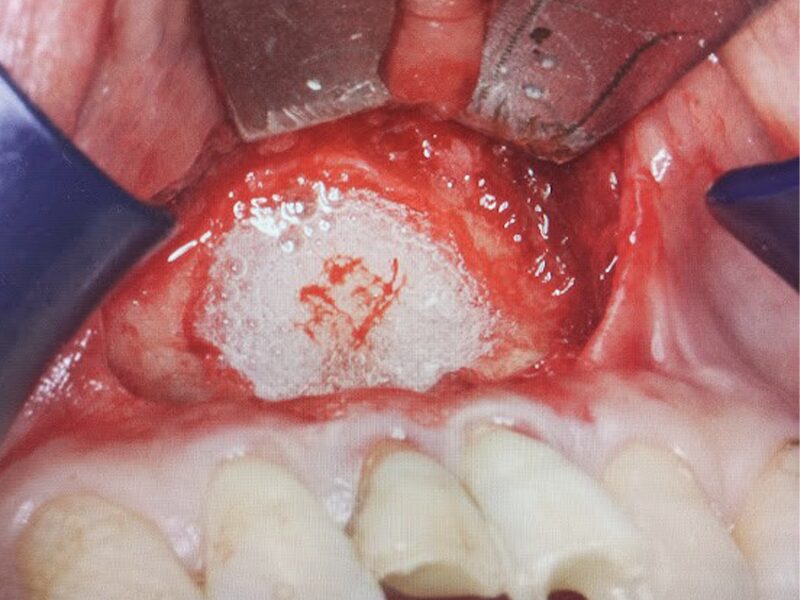

骨再生補填材を入れます。

タブレット状のボナーク(骨再生補填材)で封鎖いたします。